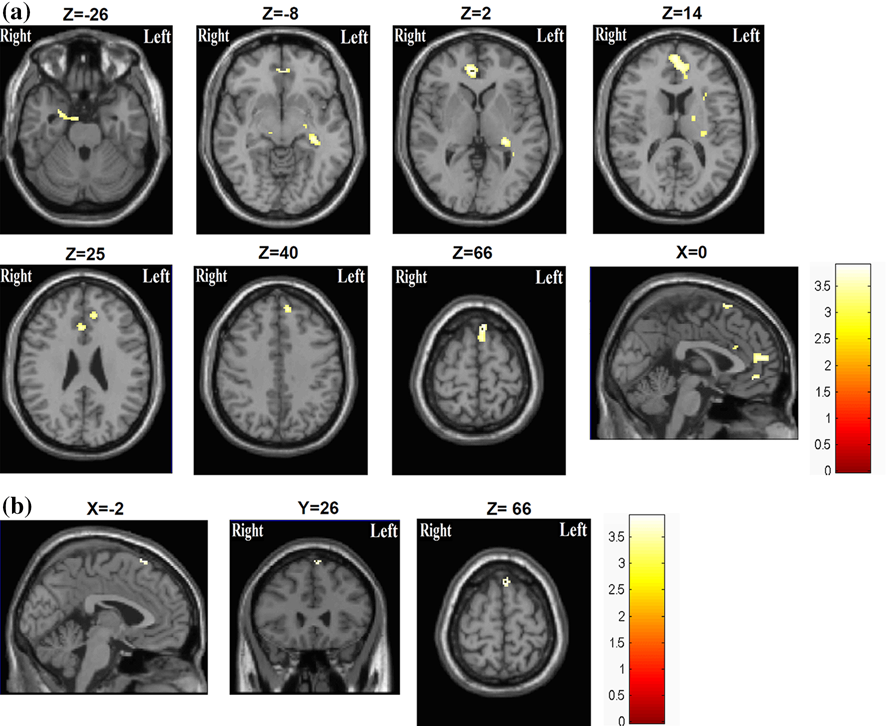

研究一:台湾高雄医科大学的Chih-Hung Ko等人在2013年中的研究发现,对成人ADHD的核磁共振扫描发现,患有ADHD的成年人在低难度言语工作记忆任务中需要付出比常人更多的努力。

另一方面,在高难度工作记忆任务中,成人ADHD电脑左前顶叶网络的大脑激活受损。

这说明了成人ADHD群体在进行工作记忆任务时,和他们的大脑异常的激活模式有关。

(a.成人多动症组的在执行语音工作记忆任务的大脑激活率高于对照组。b.成人多动症组的视觉空间工作记忆的大脑激活率高于对照组)